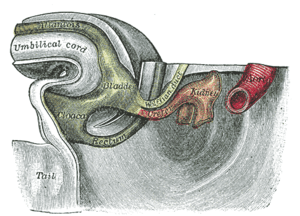

Sectional plan of the gravid human uterus in the third and fourth months of pregnancy | |

In mammals (excluding monotremes), the allantois is part of and forms an axis for the development of the umbilical cord.

- The human allantois is an endodermal evagination of the developing hindgut which becomes surrounded by the mesodermal connecting stalk known as the body-stalk. The body-stalk forms the umbilical vasculature. In other words, the allantois is a caudal diverticulum (out-pouching) of the yolk-sac. It is externally continuous with the proctodeum and internally continuous with the cloaca. The embryonic allantois becomes the fetal urachus which connects the fetal bladder (developed from cloaca) to the yolk sac. The urachus removes nitrogenous waste from the fetal bladder.[3] The allantois is vestigial and may regress, yet the homologous blood vessels persist as the umbilical arteries and veins connecting the embryo with the placenta.[4]